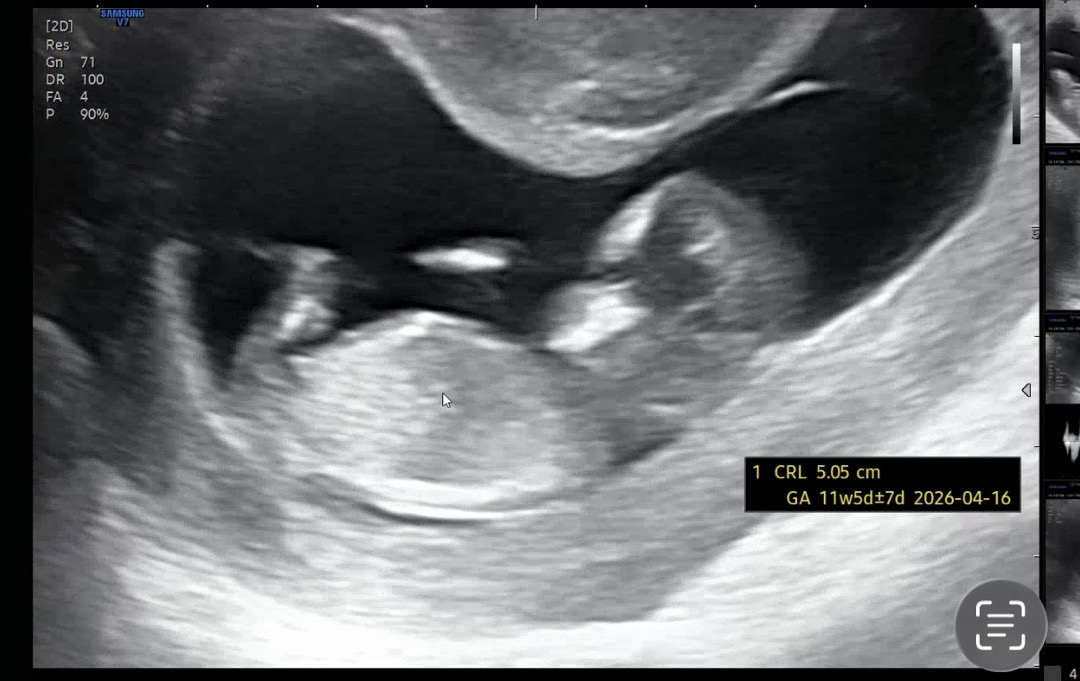

각도법 고수님들 한번만 봐주세요!

11주4일로 이르긴 하지만 궁금해서 부탁 드려봅니다..ㅎㅎ!!